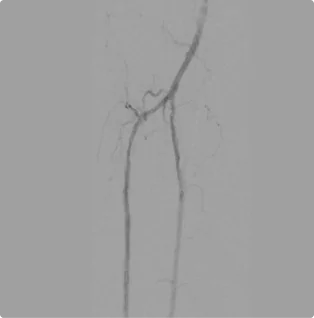

After

Arterial flow through the foot after the intervention. All three arterial branches are present and flowing smoothly, delivering proper flow to the calf and down into the foot to eliminate the need for amputation.